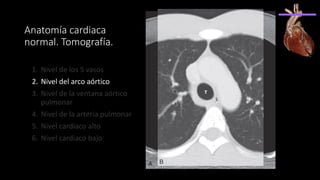

Anatomía cardiaca

normal. Tomografía.

1. Nivel de los 5 vasos

2. Nivel del arco aórtico

3. Nivel de la ventana aórtico

pulmonar

4. Nivel de la arteria pulmonar

5. Nivel cardiaco alto

6. Nivel cardiaco bajo